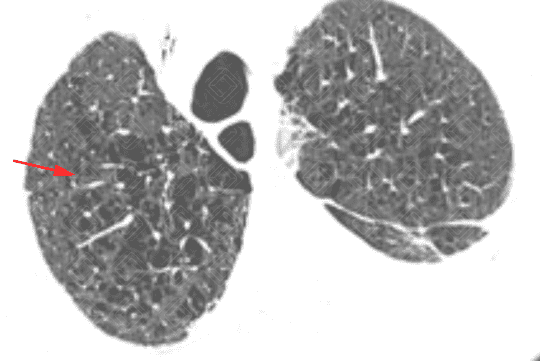

Descrição das figuras 3, 4, 5 e 6: Tomografia computadorizada do tórax seguida de aquisições coronais, sagitais e axiais mostrando as extensas áreas de enfisema centrolobular dispersas pelo parênquima pulmonar (setas vermelhas).

• Tomografia computadorizada do tórax: Este método é mais sensível e específico que a radiografia de tórax na avaliação do enfisema. Tem sido empregado para detectar, quantificar e caracterizar a doença. A tomografia é capaz de diferenciar os vários tipos de enfisema, que pode ser classificado, de acordo com a região do ácino acometida, em proximal (centrolobular ou centroacinar - figuras 3, 4, 5, 6, 9, 10 e 11 ), distal (parasseptal - figuras 7, 8, 9, 10 e 11 ) ou todo ácino (panacinar ou panlobular).